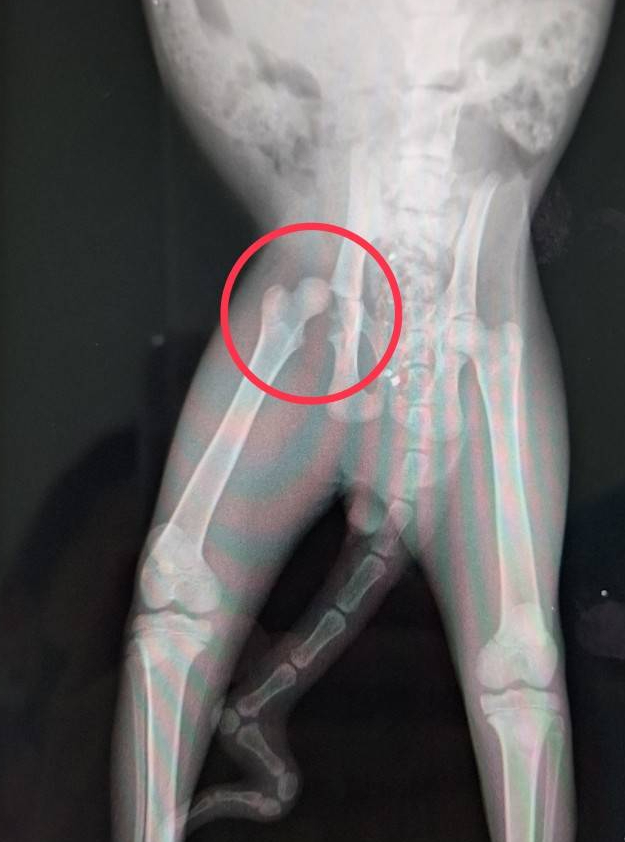

保護当初、子猫なのにすぐに横になり、血尿が出ていたのでおかしいと思いレントゲンを撮ってもらったところ、右股関節が脱臼していました。少し前のものと思われる傷も見つけ、どうやら交通事故にあったのだろうと。。

子猫のため骨が柔軟なのでこのまま生活できる場合がありますが、成長に従って痛みが出るようであれば関節切除オペを行います。当施設では過去二匹股関節のオペをやったことがあります。いつでも最高の医療をかけられるわけではありませんが、保護猫犬だからではなくできる限りの治療をしています。

ホスピスでこのまま生活ができるか様子見をしたところ、最初はジャンプもお座りも長い間できませんでしたが、今では走ることもジャンプも問題なくできています。人見知りをするため、慣れていないスタッフからは全力で逃げて隠れるくらい(笑)、痛みもなく、健康な猫と変わらない動きができています。痛みや苦しみを感じさせないよう、今後も経過は注意してみていきます。